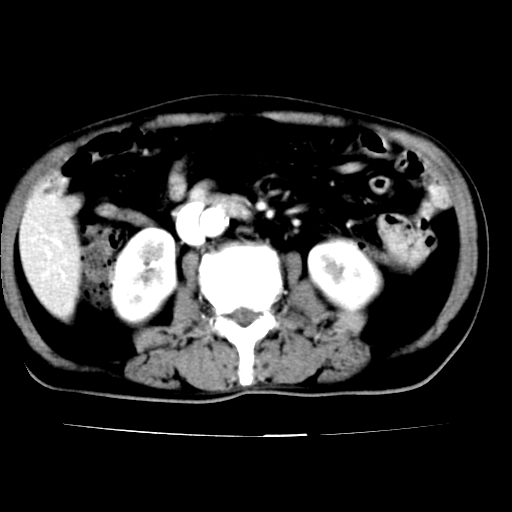

男,75岁,腹痛月余,彩超发现脐周腹主动脉异常回声。临床诊断:腹主动脉瘤。

ct诊断:右骼总动脉囊性动脉瘤并瘤内附壁血栓形成,与下腔静脉之间形成动静脉瘘。

请问各位老师:能排除动脉瘤破裂的可能吗?

各位老师注意到下腔静脉的充盈缺损了吗?注意到动静脉漏了吗?

腹总动脉瘤伴附壁血栓形成累及髂总动脉,看起来好像有动静脉瘘,但我认为是扫描时象造成的假象。

当时是扫描的标准动脉期,可是下腔静脉与腹主动脉同步强化且幅度一致。所以我想动静脉瘘是存在的。